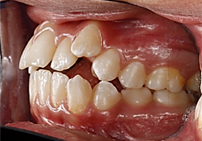

Al analizar las fotografías intraorales revelaron lo siguiente (Figura 2): Fotografía frontal: líneas medias dentales no coincidentes la inferior se encuentra con una desviación de 2 mm hacia la derecha, mordida abierta y caninos superiores ectópicos. (A). Fotografía lateral derecha (B) e izquierda (C): Clase II molar, clase canina no aplica debido a que los caninos no se encuentran en el arco.

Fotografía oclusal superior: Forma de arcada ovoide, apiñamiento en el sector anterior, palatinización de las piezas 1.2 y 2.2, piezas 1.3 y 2.3 ectópicas, paladar profundo (D). Fotografía oclusal inferior: Forma de arcada oval, lingualización de las piezas 4.5 y 4.6, ausencia de la pieza 3.7 (E). Fotografía de resalte: La sobremordida horizontal y vertical de -2 mm (F).